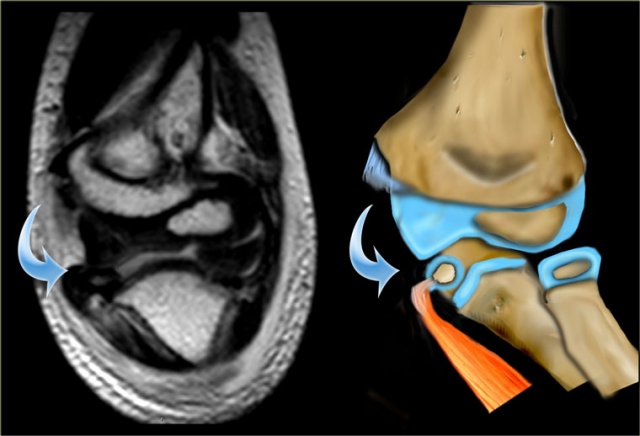

MR of  lateral condyle fracture. Milch II and unstable elbow. T2  image with fat saturation on the right shows cartilaginous fracture.  Fracture-fragment surrounded by synovial fluid. (Courtesy of  Lynne Steinbach, M.D. Univ. of California, San Francisco) MR of lateral condyle fracture. Milch II and unstable elbow. T2 image with fat saturation on the right shows cartilaginous fracture. Fracture-fragment surrounded by synovial fluid. (Courtesy of Lynne Steinbach, M.D. Univ. of California, San Francisco)

MRI can be helpfull in depicting the full extent of the cartilaginous component of the fracture.

The case on the left shows a fracture extending into the unossified trochlear ridge.

The fracture through the trochlear cartilage is so far medial that the ulna is only supported on the medial side.

This means that the elbowjoint is unstable.